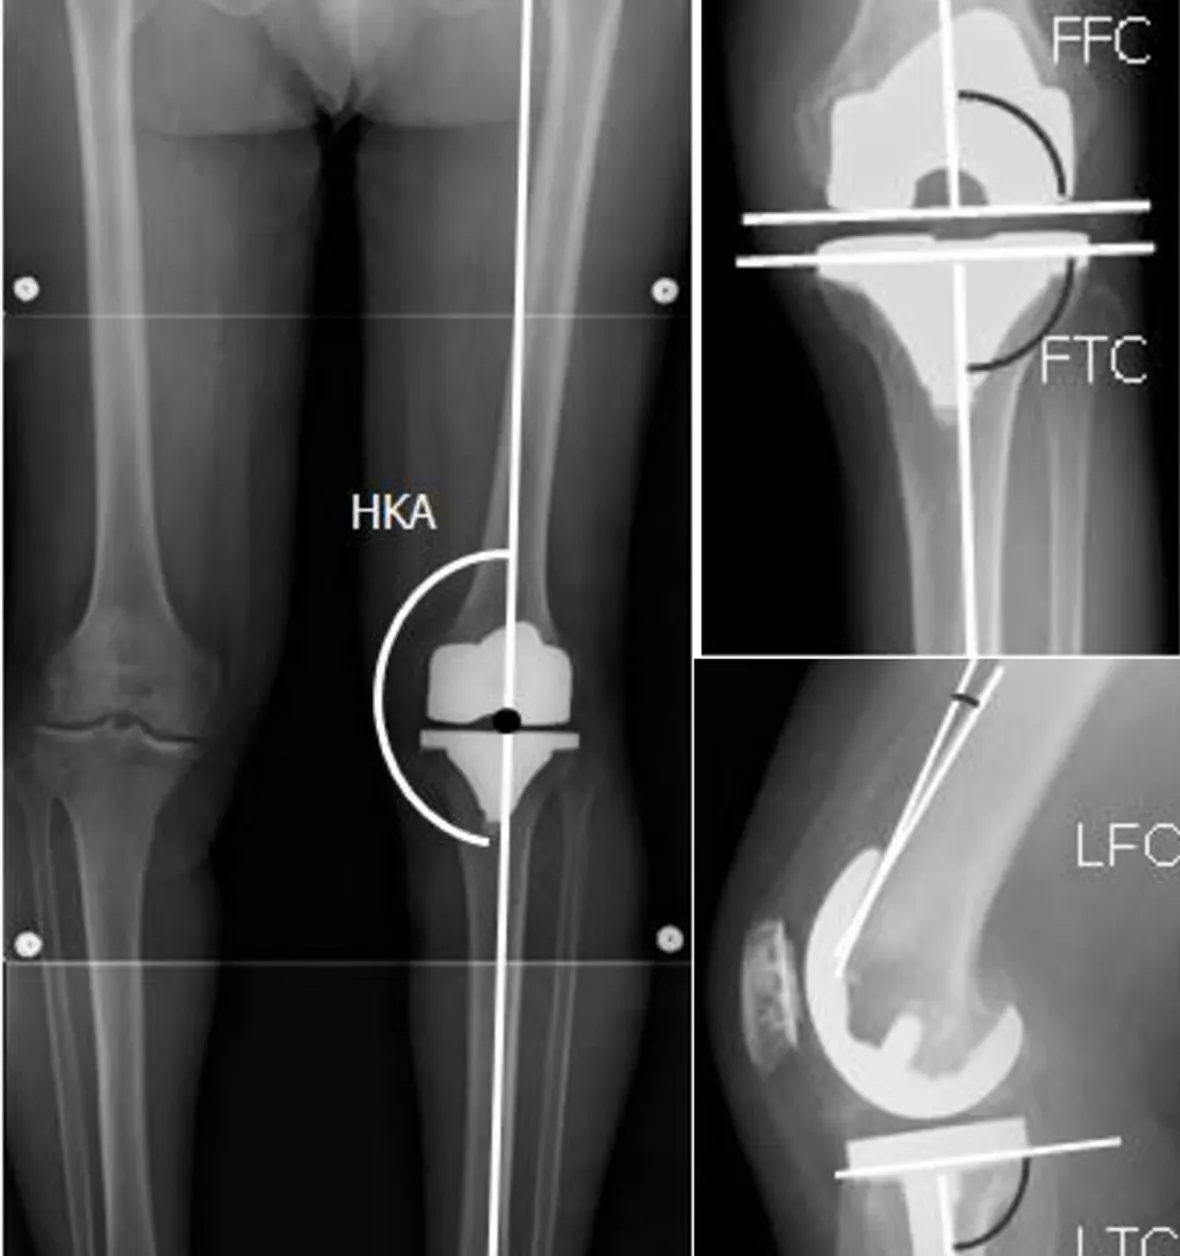

Successful knee replacement recovery depends on restoring balanced movement through the hips, ankles, and ribcage—not just the knee itself. Xray Image Credit WikiCommons